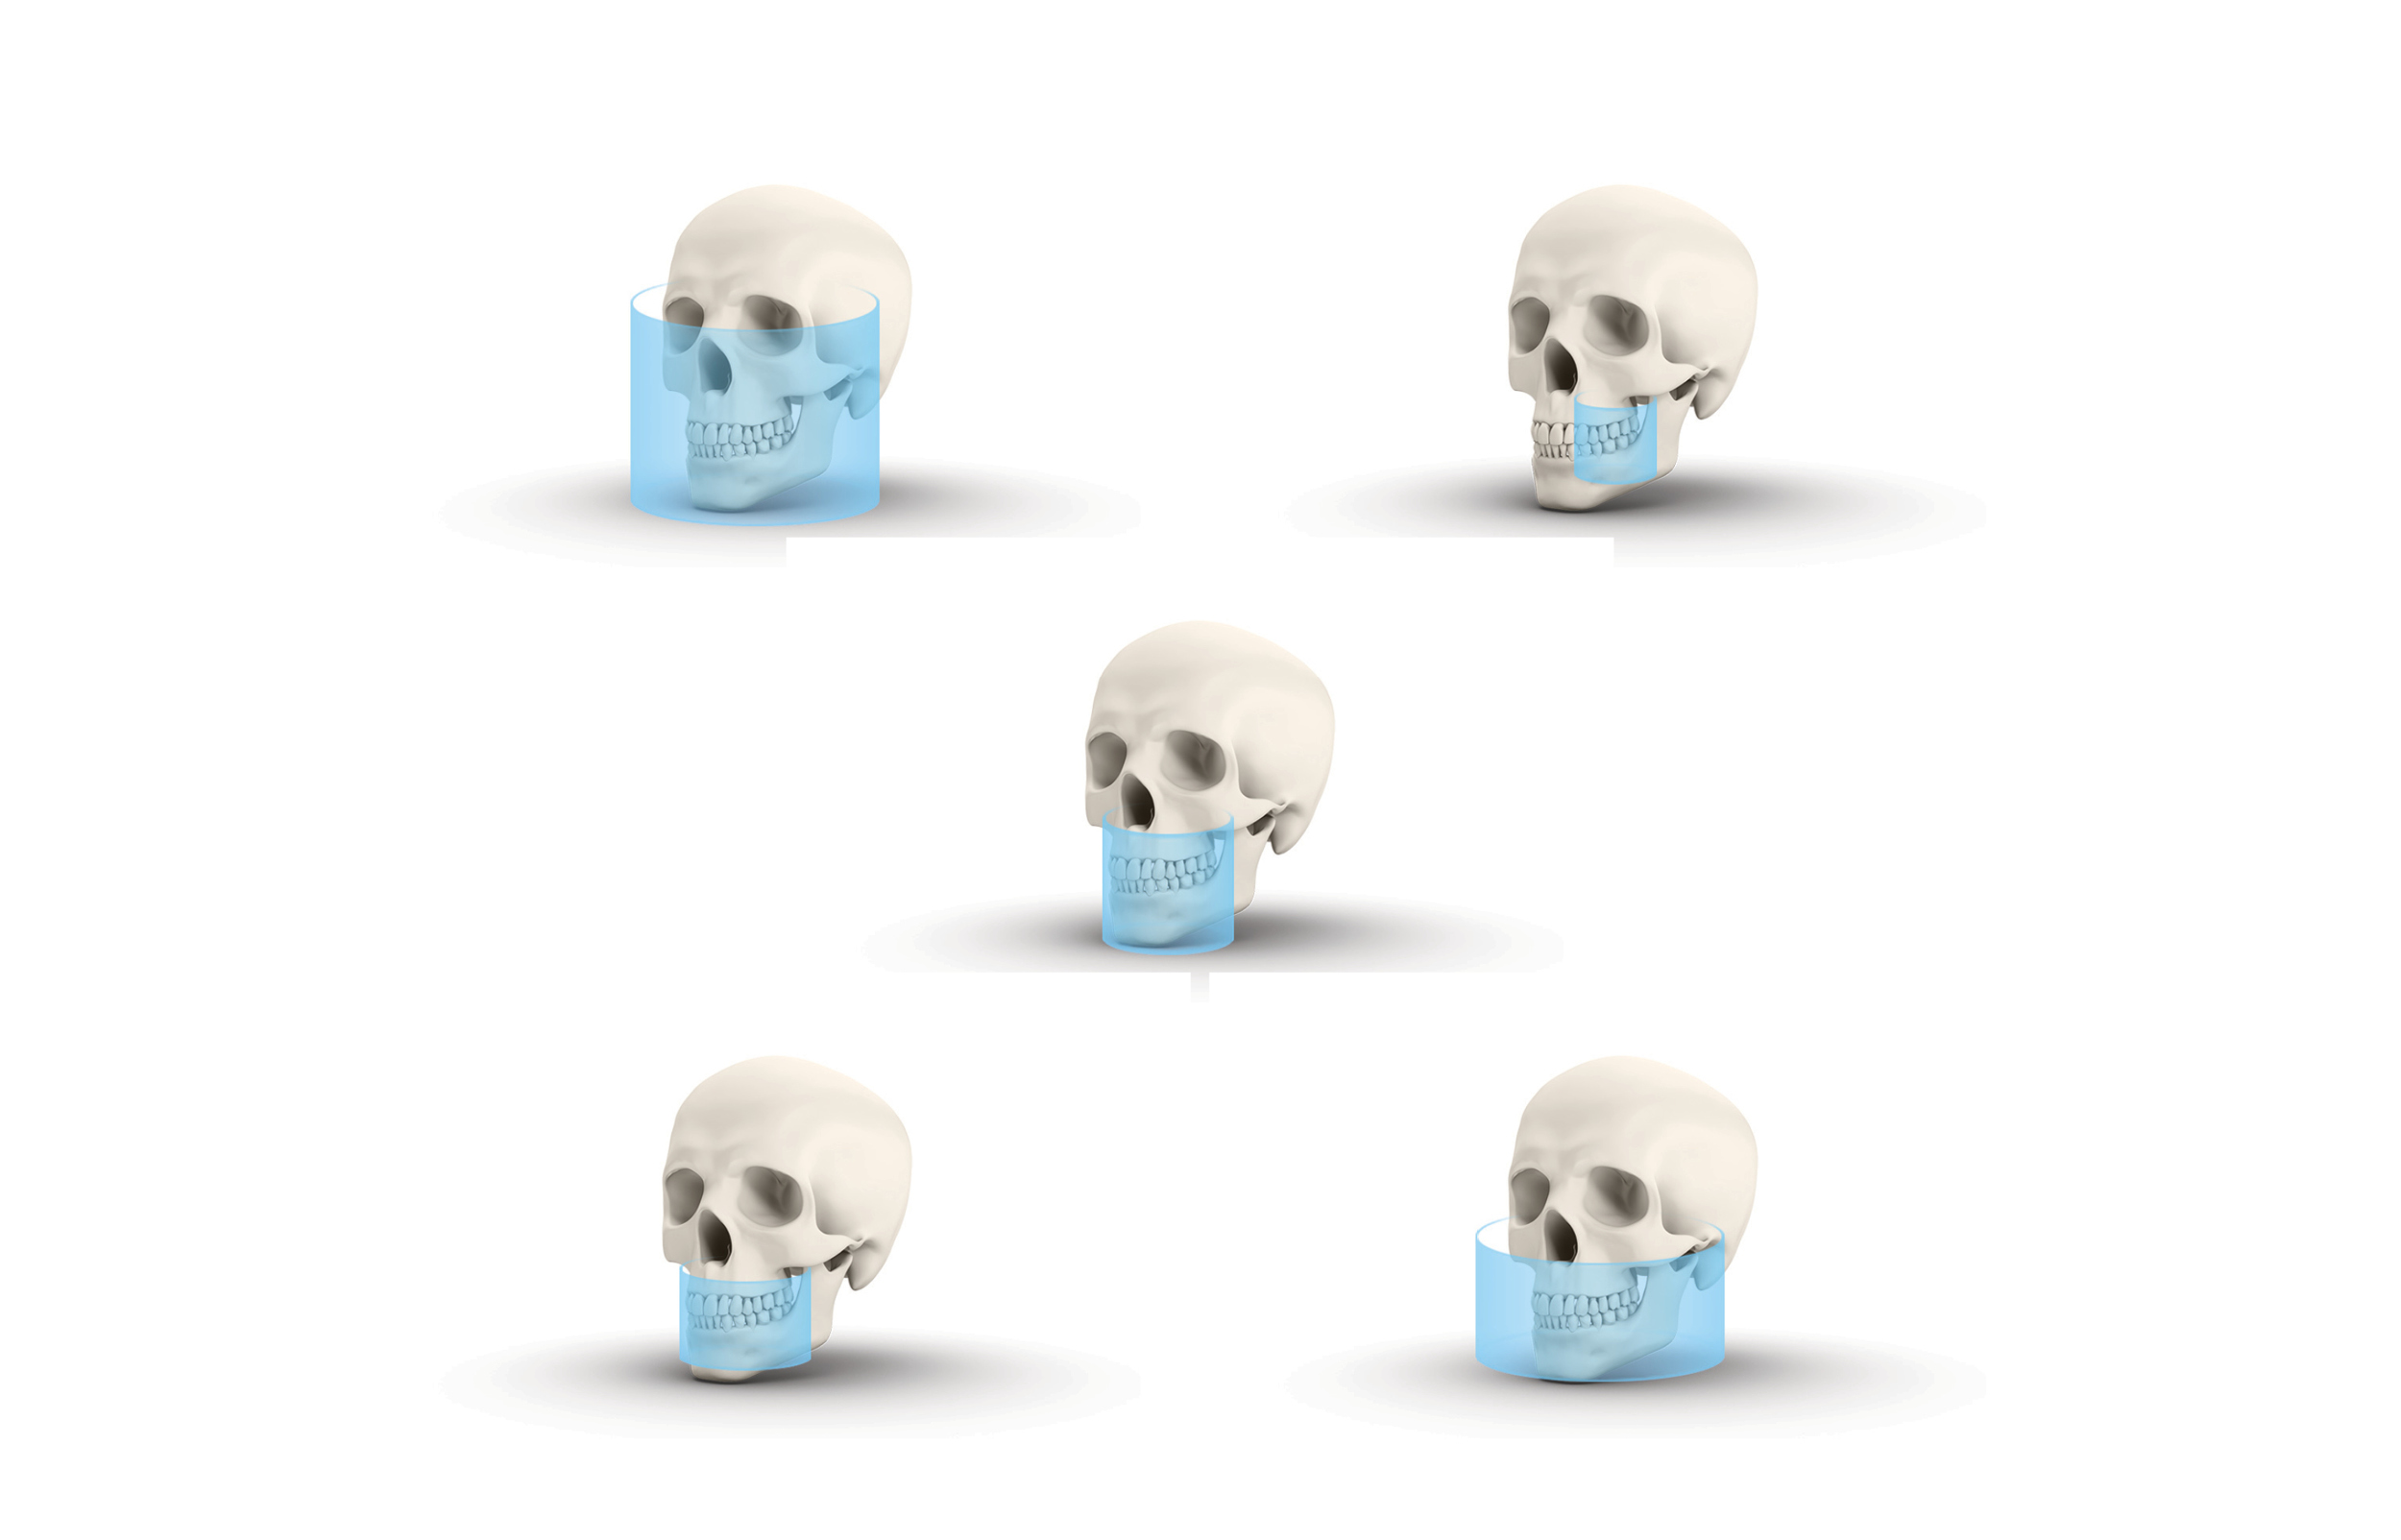

Five field of views — multiple possibilities

For all five volume sizes, you can choose from three image resolutions. With the 5 x 5 cm (6 x 4 cm) volume, there is an endo resolution available. Each setting provides the perfect resolution in relation to the relevant indication. The five volume sizes ensure reliable 3D diagnosis throughout the maxillofacial region.